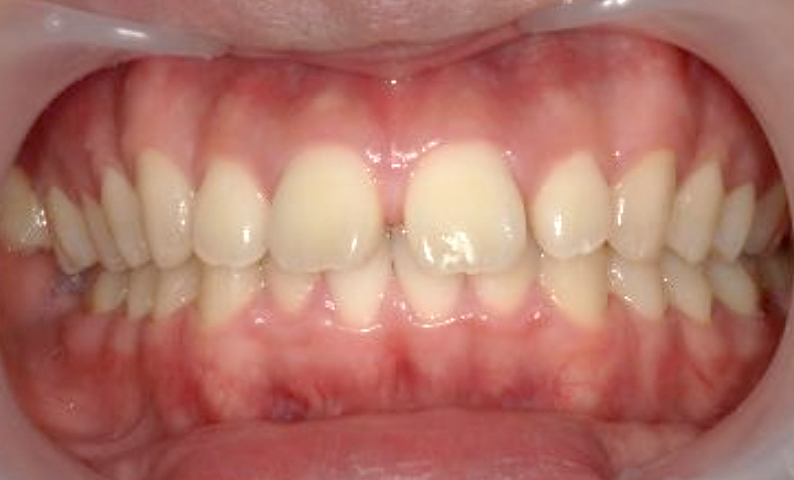

| 治療前 | 治療後 |

|---|---|

|